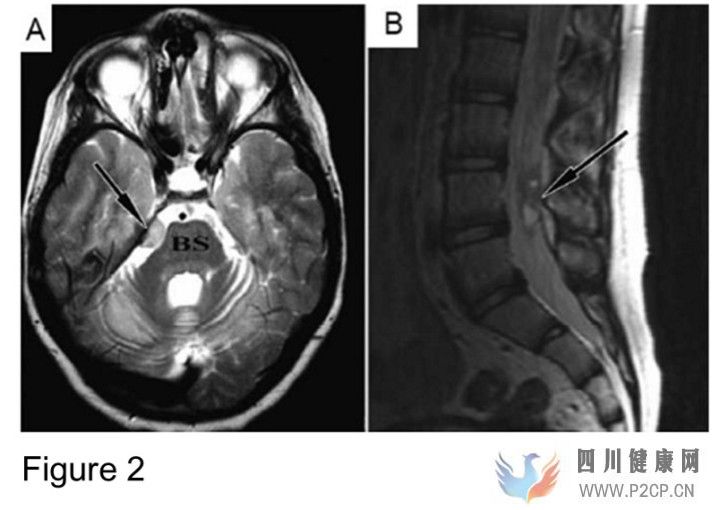

这并不是孤例。在2009年的时候,以色列的医生接收了一名13岁的小男孩,他因为头疼被诊断出脑癌,根据病人父母的陈述,小男孩在9岁时患上了失调性毛细管扩张症(ataxia-telangiectasia),这种小儿病症会造成控制肌肉运动和语言能力的相关脑组织退化。于是绝望的父母带他去了莫斯科,先后四次接受了经颅和经椎管注射神经干细胞的手术。四年以后,以色列医生通过MRI成像很快在脑中和脊柱中发现了神经胶质瘤的存在(Figure 2)。活检也发现了肿瘤的存在(Figure 3)。此后一系列的分子生物学实验更是从癌细胞中发现了外源细胞的存在,证明小男孩接受了至少两个不同人来源的神经干细胞[2]。小男孩现在只能坐在轮椅上,更不幸的是,他还多了个癌症。